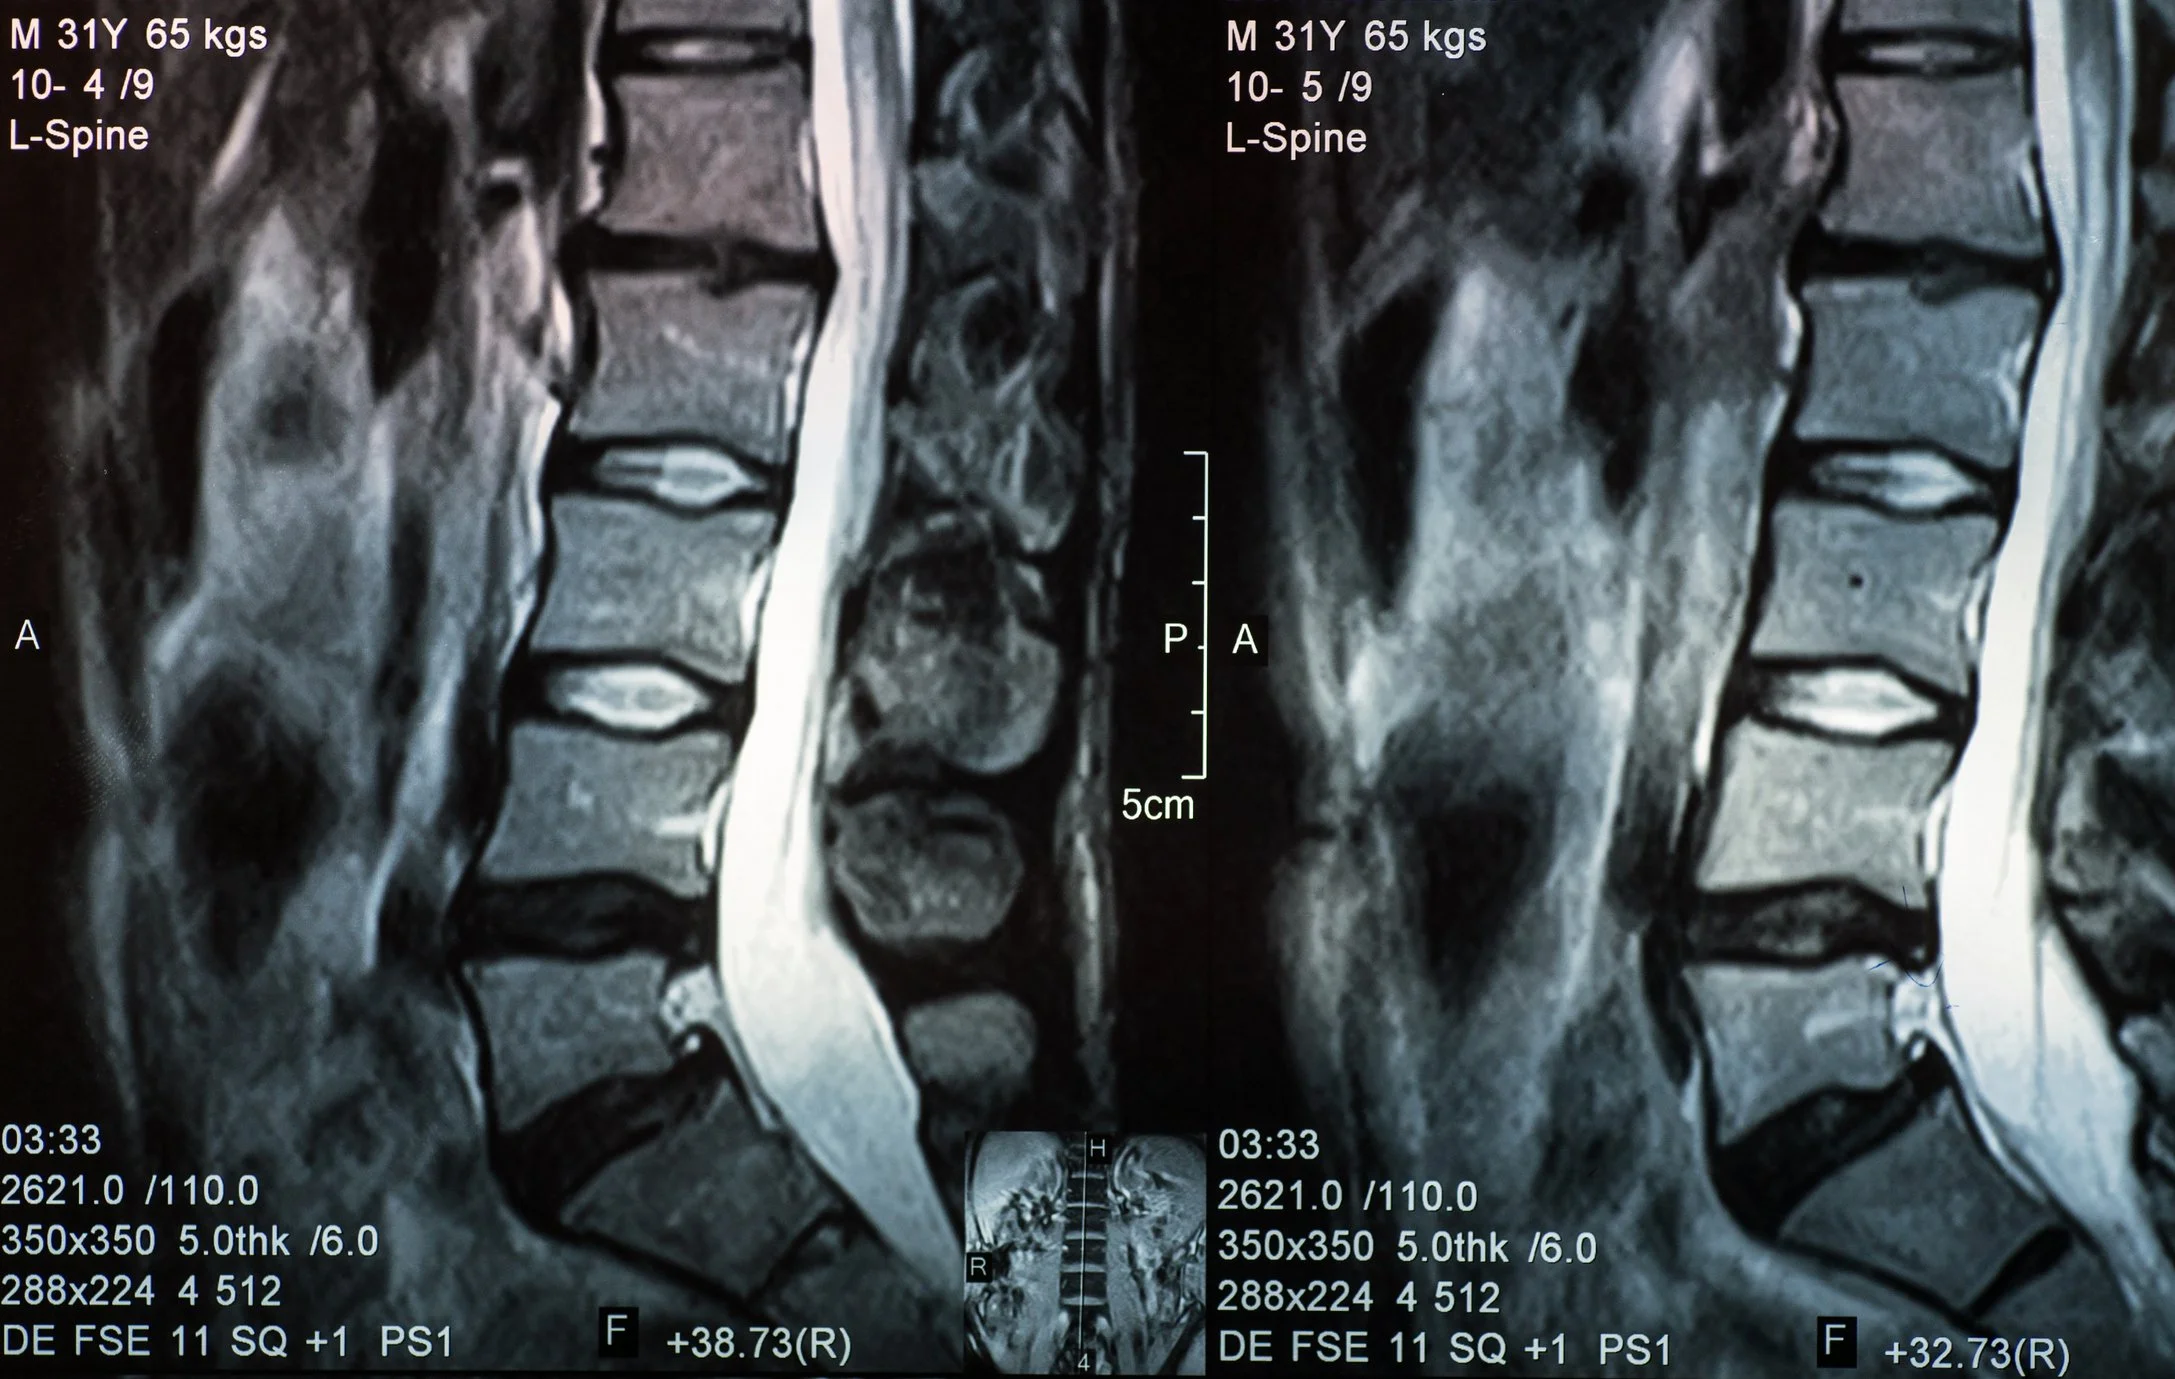

Most people over 30–40 will show things like:

Disc bulges

Disc degeneration

Facet joint arthritis

Annular tears

These findings are extremely common in people with NO pain.

The severity of MRI changes does not correlate well with pain

People with “bad-looking” scans often do very well

People with “normal” scans can have severe pain